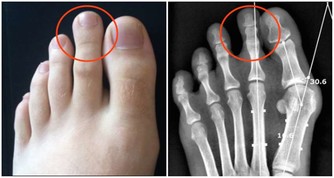

重缺鋅會影響前列腺健康,或導致孩子偏食、有吃土等異食癖。